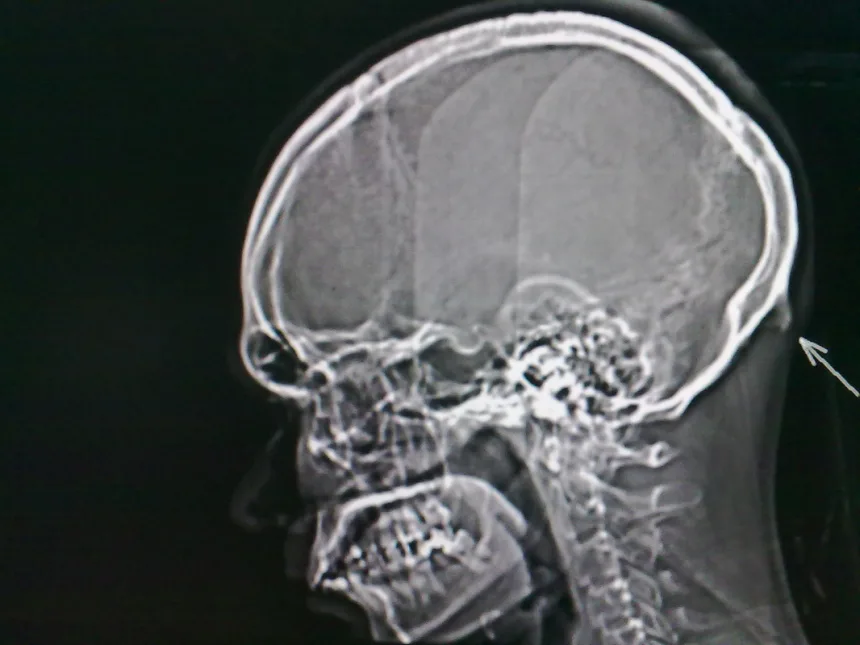

Malý výrastok, ktorý bežne nazývame záhlavná kosť (protuberantia occipitalis externa) je bežnou súčasťou ľudskej anatómie. Čo však nie je až také bežné je to, do akých rozmerov dokáže pri moderných ľuďoch narásť.

Presný pôvod nadmerného rastu záhlavnej kosti zatiaľ nie je jasný, no vedci a doktori majú veľmi reálnu teóriu. K rastu má dochádzať pri neprirodzenom skláňaní hlavy, čo robíme hlavne pri používaní inteligentných zariadení. Ľudská hlava je prekvapivo ťažká, v priemere až 4,5 kg, kvôli čomu môže mať jej nadmerné skláňanie nepriaznivé účinky na naše zdravie.

Fenomén, keď si ľudia nadmerne zaťažia svaly v krku pozeraním do telefónu vedci nazvali „Text neck,“ vo voľnom preklade teda sms-kový krk. Dochádza k nemu vtedy, keď sa pri sklonení hlavy vyvinie väčší tlak na miesto, kde sa svaly pripájajú k lebke. Telo má na tento jav reagovať nadmerným rastom spomínanej kosti.

Pri pohľade na výsledky mladých pacientov vo veku od 18 do 30 rokov ostali vedci a doktori trochu zaskočení. Záhlavná kosť v priemere bežne meria približne 5 milimetrov. Pri zväčšení sa jej veľkosť pohybuje na úrovni 10 mm.

Z 218 meraní došlo k zväčšeniu u 41 % z ľudí. 10 % z nich malo záhlavnú kosť veľkú až 20 mm. Zväčšenie záhlavnej kosti je častejšie u mužov. Najväčšia z nich v priemere merala až 35,7 mm.